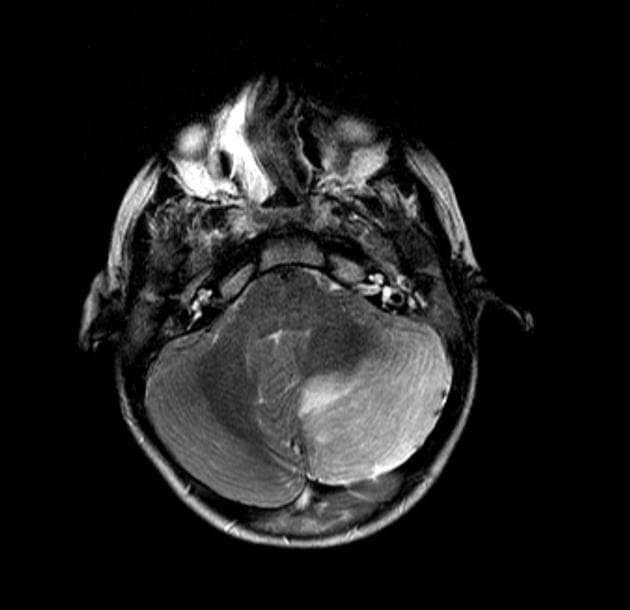

Axial T2

Temporal bone rhabdomyosarcoma with leptomeningeal metastases

Có một khối u dạng thùy, tăng quang không đồng nhất, khu trú tại ống tai ngoài, hòm nhĩ, các tế bào chũm và tai trong bên trái. Khối u có tín hiệu thấp trên các hình ảnh T1 và tín hiệu cao trên các chuỗi T2 và FLAIR. Đã ghi nhận sự xâm lấn vào góc cầu tiểu não bên trái. Có hiệu ứng khối đi kèm gây chèn ép lên não giữa, cầu não và não thất tư.

Phía trước, khối u tiếp giáp với thùy thái dương dưới. Sự xâm lấn vào phía trong dẫn đến tiếp giáp với khoang động mạch cảnh bên trái, với các khoảng trống tín hiệu dòng chảy vẫn được bảo tồn trong các mạch máu lân cận. Xâm lấn ra phía trước ngoài liên quan đến tuyến mang tai kèm theo một hạch bạch huyết tuyến mang tai lớn. Có tăng quang màng não dạng nốt dày dọc theo lều tiểu não bên trái, thân não, màng não vùng nền, vòm sọ và bán cầu tiểu não, phù hợp với lan tỏa màng não mềm.

THẢO LUẬN: Kết quả giải phẫu bệnh xác nhận sarcoma cơ vân. Hình ảnh cho thấy một khối u ác tính tiến triển mạnh khu trú tại nền sọ với sự lan rộng tại chỗ và xâm lấn nội sọ. Sarcoma cơ vân là loại sarcoma mô mềm phổ biến nhất ở trẻ em và thanh thiếu niên, thường liên quan đến vùng đầu cổ, bao gồm các vị trí cạnh màng não như tai giữa, xương chũm và khoang quanh hầu.

Các khối u cạnh màng não có nguy cơ xâm lấn nội sọ và lan tỏa màng não mềm cao hơn, như đã thấy trong trường hợp này. Hình thái dạng thùy, tăng quang không đồng nhất, bao quanh mạch máu nhưng vẫn bảo tồn khoảng trống tín hiệu dòng chảy, lan truyền quanh dây thần kinh và nền sọ, liên quan hạch vùng và tăng quang màng não dạng nốt lan tỏa là những đặc điểm của bệnh giai đoạn muộn. Sự xâm lấn nội sọ vào góc cầu tiểu não và các cấu trúc hố sau, cùng với hiệu ứng khối lên thân não và não thất tư, phản ánh tính chất xâm lấn mạnh. Di căn màng não mềm ảnh hưởng đáng kể đến việc phân giai đoạn và tiên lượng, đồng thời đòi hỏi chẩn đoán hình ảnh toàn bộ trục thần kinh và quản lý ung thư đa chuyên khoa.